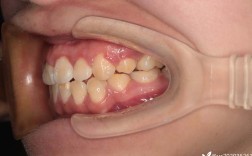

长期缺牙还会导致邻牙向缺牙区倾斜、对颌牙伸长,进而改变咬合关系,引发颞下颌关节紊乱、食物嵌塞、牙周炎等问题,牙槽骨吸收还会导致面部软组织失去支撑,出现“瘪嘴”、面部凹陷等衰老外观,影响美观和心理状态。

邻牙及口腔整体健康受损

缺牙区邻牙失去“依靠”后会向缺隙倾斜,导致牙缝变大、食物嵌塞,增加邻牙龋坏和牙周病风险;对颌牙因失去咬合对抗会伸长,可能咬伤对侧牙龈,或导致咬合紊乱,引发颞下颌关节弹响、疼痛等问题。